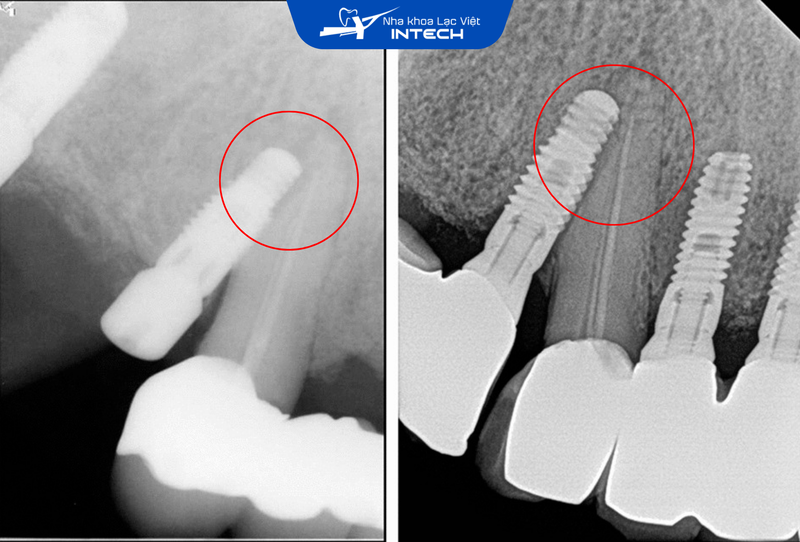

Nếu kỹ thuật đặt trụ không chính xác, trụ Implant có thể bị lệch về phía các chân răng tự nhiên bên cạnh, gây ra các biến chứng nguy hiểm